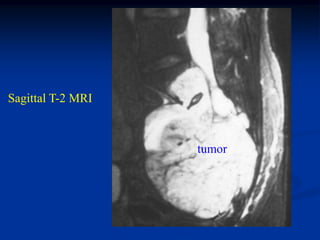

82 year male with chordoma lower sacrum

Lateral view

Sagittal T-1 MRI

Sagittal T-2 MRI

tumor